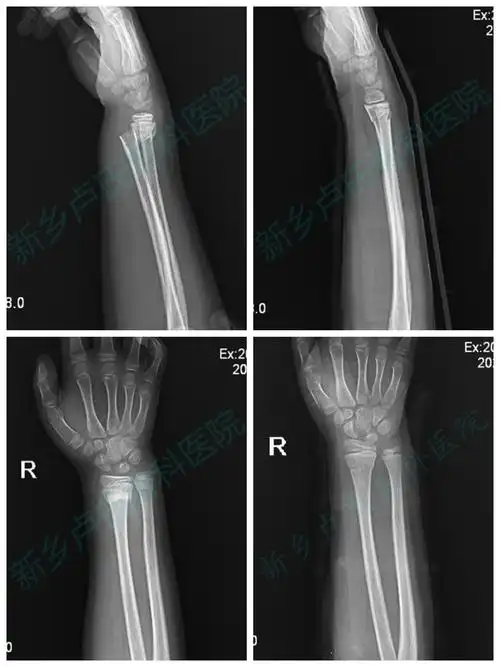

桡骨远端骨折c3型病例分享

右尺桡骨远端骨折

(秦海泉)尺桡骨远端开放性粉碎性骨折

右侧桡骨远端骨折

中老年人尺桡骨远端骨折1例分析

桡骨远端骨折(ao分型c1)

儿童尺桡骨远端骨折